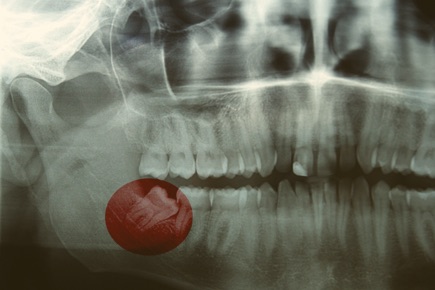

Wisdom teeth usually erupt between the ages of 17 and 25, with most adults growing four. Some people may grow fewer than this number, or none at all. They often become impacted or may cause crowding of other teeth. Wisdom teeth are removed either by a dentist or dental surgeon.